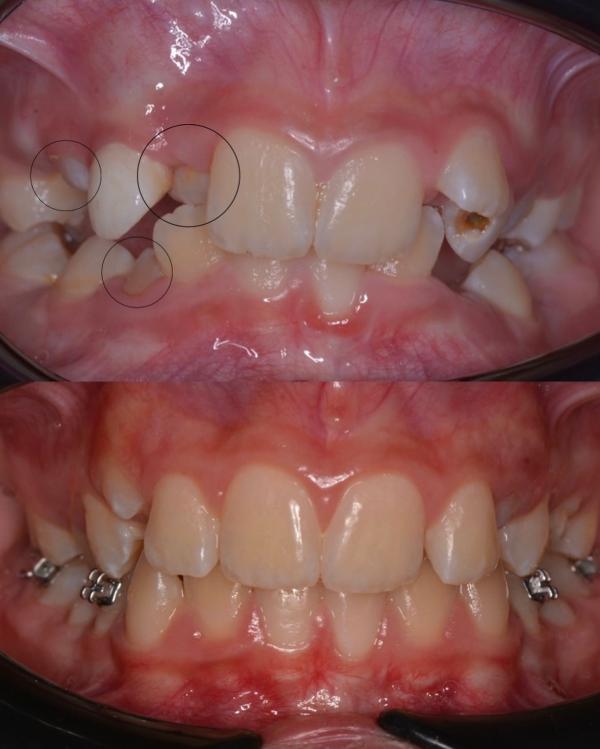

Перевоплощение длиной в 3 года …

Лечение , которое можно было бы избежать…💔

Итак , вернёмся в начало. 🖌

К этой пациентке я прониклась особенной любовью с первого визита ❤️☀️, солнечную девочку зовут Насиба, ей было на тот момент 9 лет

Пришёл ребёнок на консультацию, вижу множество проблем:

🦔Сужение верхней челюсти

🦔Дефицит места для прорезывания зубов

🦔Глубокий травматический прикус

🦔Рецесс...